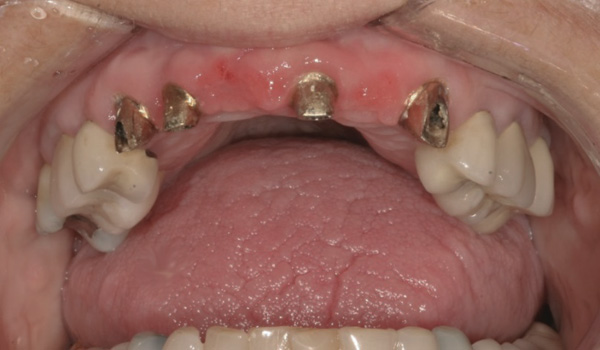

Background: The patient in this case presented with a failing dentition due to generalized severe periodontal disease with secondary endodontic lesions. She adamantly refused to wear removable transitional prostheses. Full maxillary and mandibular extractions were performed in the first phase of treatment. Not all implants could be placed in this initial phase due to the need for healing of certain grafted sites. The implants placed in this first phase were loaded with conical abutments and, in some cases, their angulated counterparts (Figure 16 and Figure 17). These stock titanium abutments were selected to avoid the need, as in Case 3, to change or remill the more costly custom abutments. They also have the advantage of making it unnecessary to use temporary cement near and around surgical sites, as they use occlusal screws only for retention.

Results: Stock titanium abutments were used until all tissue healing was achieved and the secondary implants had healed. Figure 18 shows the maxillary and mandibular custom abutments inserted. Figure 19 shows a close-up of the patient’s right side quadrants, depicting the final case 15 months after initial treatment began. Recession can be seen around units corresponding to tooth Nos. 5 and 6. In this case, the authors attempted to minimize recession susceptibility by employing stock temporary screw-retained abutments during healing phases throughout the initial stages of the treatment plan. Despite these efforts, recession still occurred in certain areas where the implants were labially placed. Since the photographs shown in this case were taken, an unsuccessful attempt was made by the patient’s surgeon to graft soft tissue around these sites with recession.

Quantity of buccal bone—Le and Borzabadi-Farahani concluded that a minimum of 2 mm of facial bone is necessary to prevent future recession.23 Bashutski and Wang noted that the most common esthetic complication is gingival recession, and cited inadequate buccal bone thickness, implants placed too far buccally, and failure to graft “jumping distance” during immediate placement in the etiology of recession.22 Case 5’s final result (Figure 19) shows more than 2 mm of labial recession around the implant-supported abutments at site Nos. 5 and 6 (this was also the case at site Nos. 13 and 14). Referring back to Figure 17, it is apparent that site Nos. 5, 6, 8, and 12 demonstrate very little buccal soft tissue due to the labial placement of the implants. Butler and Kinzer support the premise that there must be adequate bone volume facially, even when the implant is placed ideally, and they found that many complications are related more to the implant position and the associated anatomical findings.21

Buccal-labial position of implants—Saadoun and Touati concluded that the buccal orientation of the implant will impinge upon the buccal cortical wall and induce bone resorption and apical migration of the tissue.13 Chu et al reported that if the implant is not placed more palatally and 3-mm to 4-mm apical to the free gingival margin to assure the proper emergence profile, the esthetic outcome may be compromised.34 Bengazi et al’s 2-year longitudinal study demonstrated that anteriorly positioned implants demonstrated slightly more recession than implants in posterior positions.17 Buccal implant placement can be clearly seen in Case 5 (Figure 17) with healing abutments in place.

Proximity to adjacent implants—Tarnow et al24 and Tarnow et al25 recommend that a minimum of 3 mm of bone exist between two adjacent implants. In site Nos. 13 and 14 (Case 5) the fixture heads have less than 2 mm between them, and the abutments have less than 1 mm (Figure 17). Because interdental tissues do not have the same level of support between implants as they do with natural teeth, interdental distance becomes more critical in predicting the final soft-tissue position.

Figure 16 First-phase implants loaded with conical abutments and, in some cases, their angulated counterparts.

Figure 16

Figure 17 First-phase implants loaded with conical abutments and, in some cases, their angulated counterparts.

Figure 17

Figure 18 Custom abutments inserted.

Figure 18

Figure 19 Final result 15 months after initial treatment began, showing patient’s right side quadrants.

Figure 19